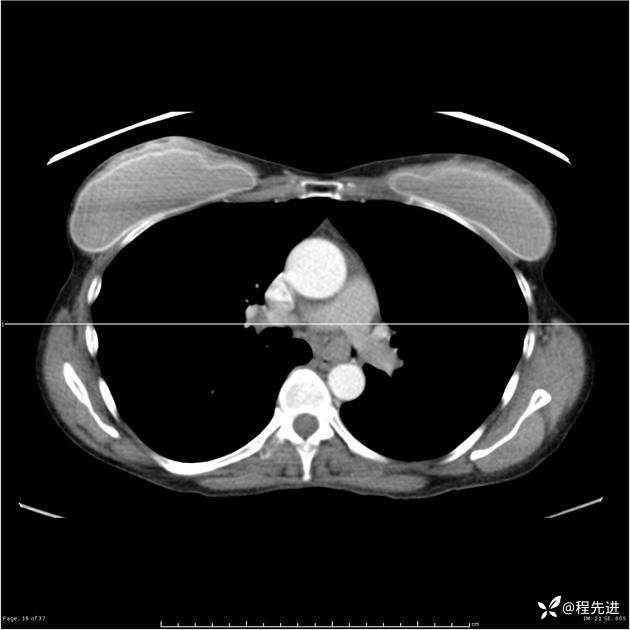

病例女,53岁,气管、左主支气管、下叶支气管内结节,乳头状瘤?期待你的精彩解读

女,53岁

乳头状瘤?